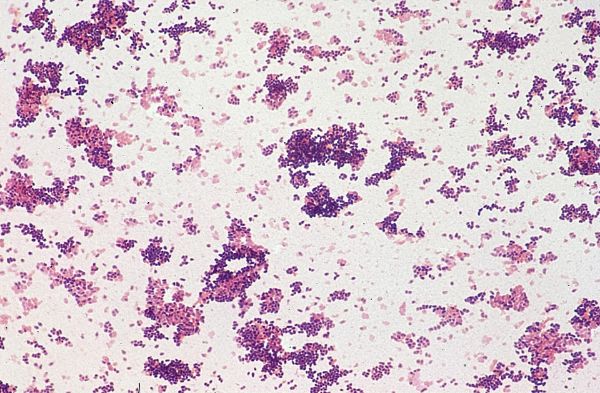

Cocci à Gram positif coccoïde ou ovoïde, anaérobie aéro tolérant et capsulé, appartenant au genre Streptococcus. Sur la base des polysaccharides capsulaires, 35 sérotypes ont été identifiés (les sérotypes 32 et 34 ont depuis été reclassifiés comme Streptococcus orisratti). Les souches les plus prévalentes chez l’homme et le porc à travers le monde appartiennent au sérotype 2 (1–3).